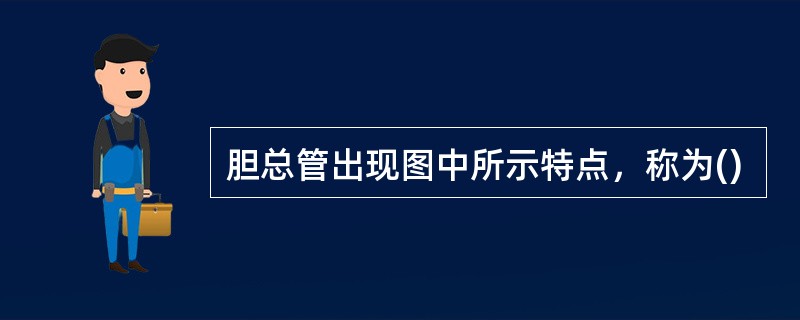

胆总管出现图中所示特点,称为()

A .双筒枪征

B .海鸥征

C .鸟嘴征

D .鼠尾征

E .平行管征

胆总管出现图中所示特点,称为()。

[单选题]胆总管出现图中所示特点,称为()。A . 双筒枪征B . 海鸥征C . 鸟嘴征D . 鼠尾征E . 平行管征

胆总管出现图中所示特点,称为()

[单选题]胆总管出现图中所示特点,称为()A . 双筒枪征B . 海鸥征C . 鸟嘴征D . 鼠尾征E . 平行管征

胆总管出现图中所示特点,称为( )。<br /><img border="0" style="width: 485px; height: 377px;

[单选题]胆总管出现图中所示特点,称为( )。A.双筒枪征B.海鸥征C.鸟嘴征D.鼠尾征E.平行管征

胆总管出现图中所示特点,称为()<img border="0" style="width: 407px; height: 305px;" src=&quo

[单选题]胆总管出现图中所示特点,称为()A.双筒枪征B.海鸥征C.鸟嘴征D.鼠尾征E.平行管征

胆总管出现图中所示特点,称为( )。<br /><img border="0" style="width: 485px; height: 377px;

[单选题]胆总管出现图中所示特点,称为( )。A.双筒枪征B.海鸥征C.鸟嘴征D.鼠尾征E.平行管征